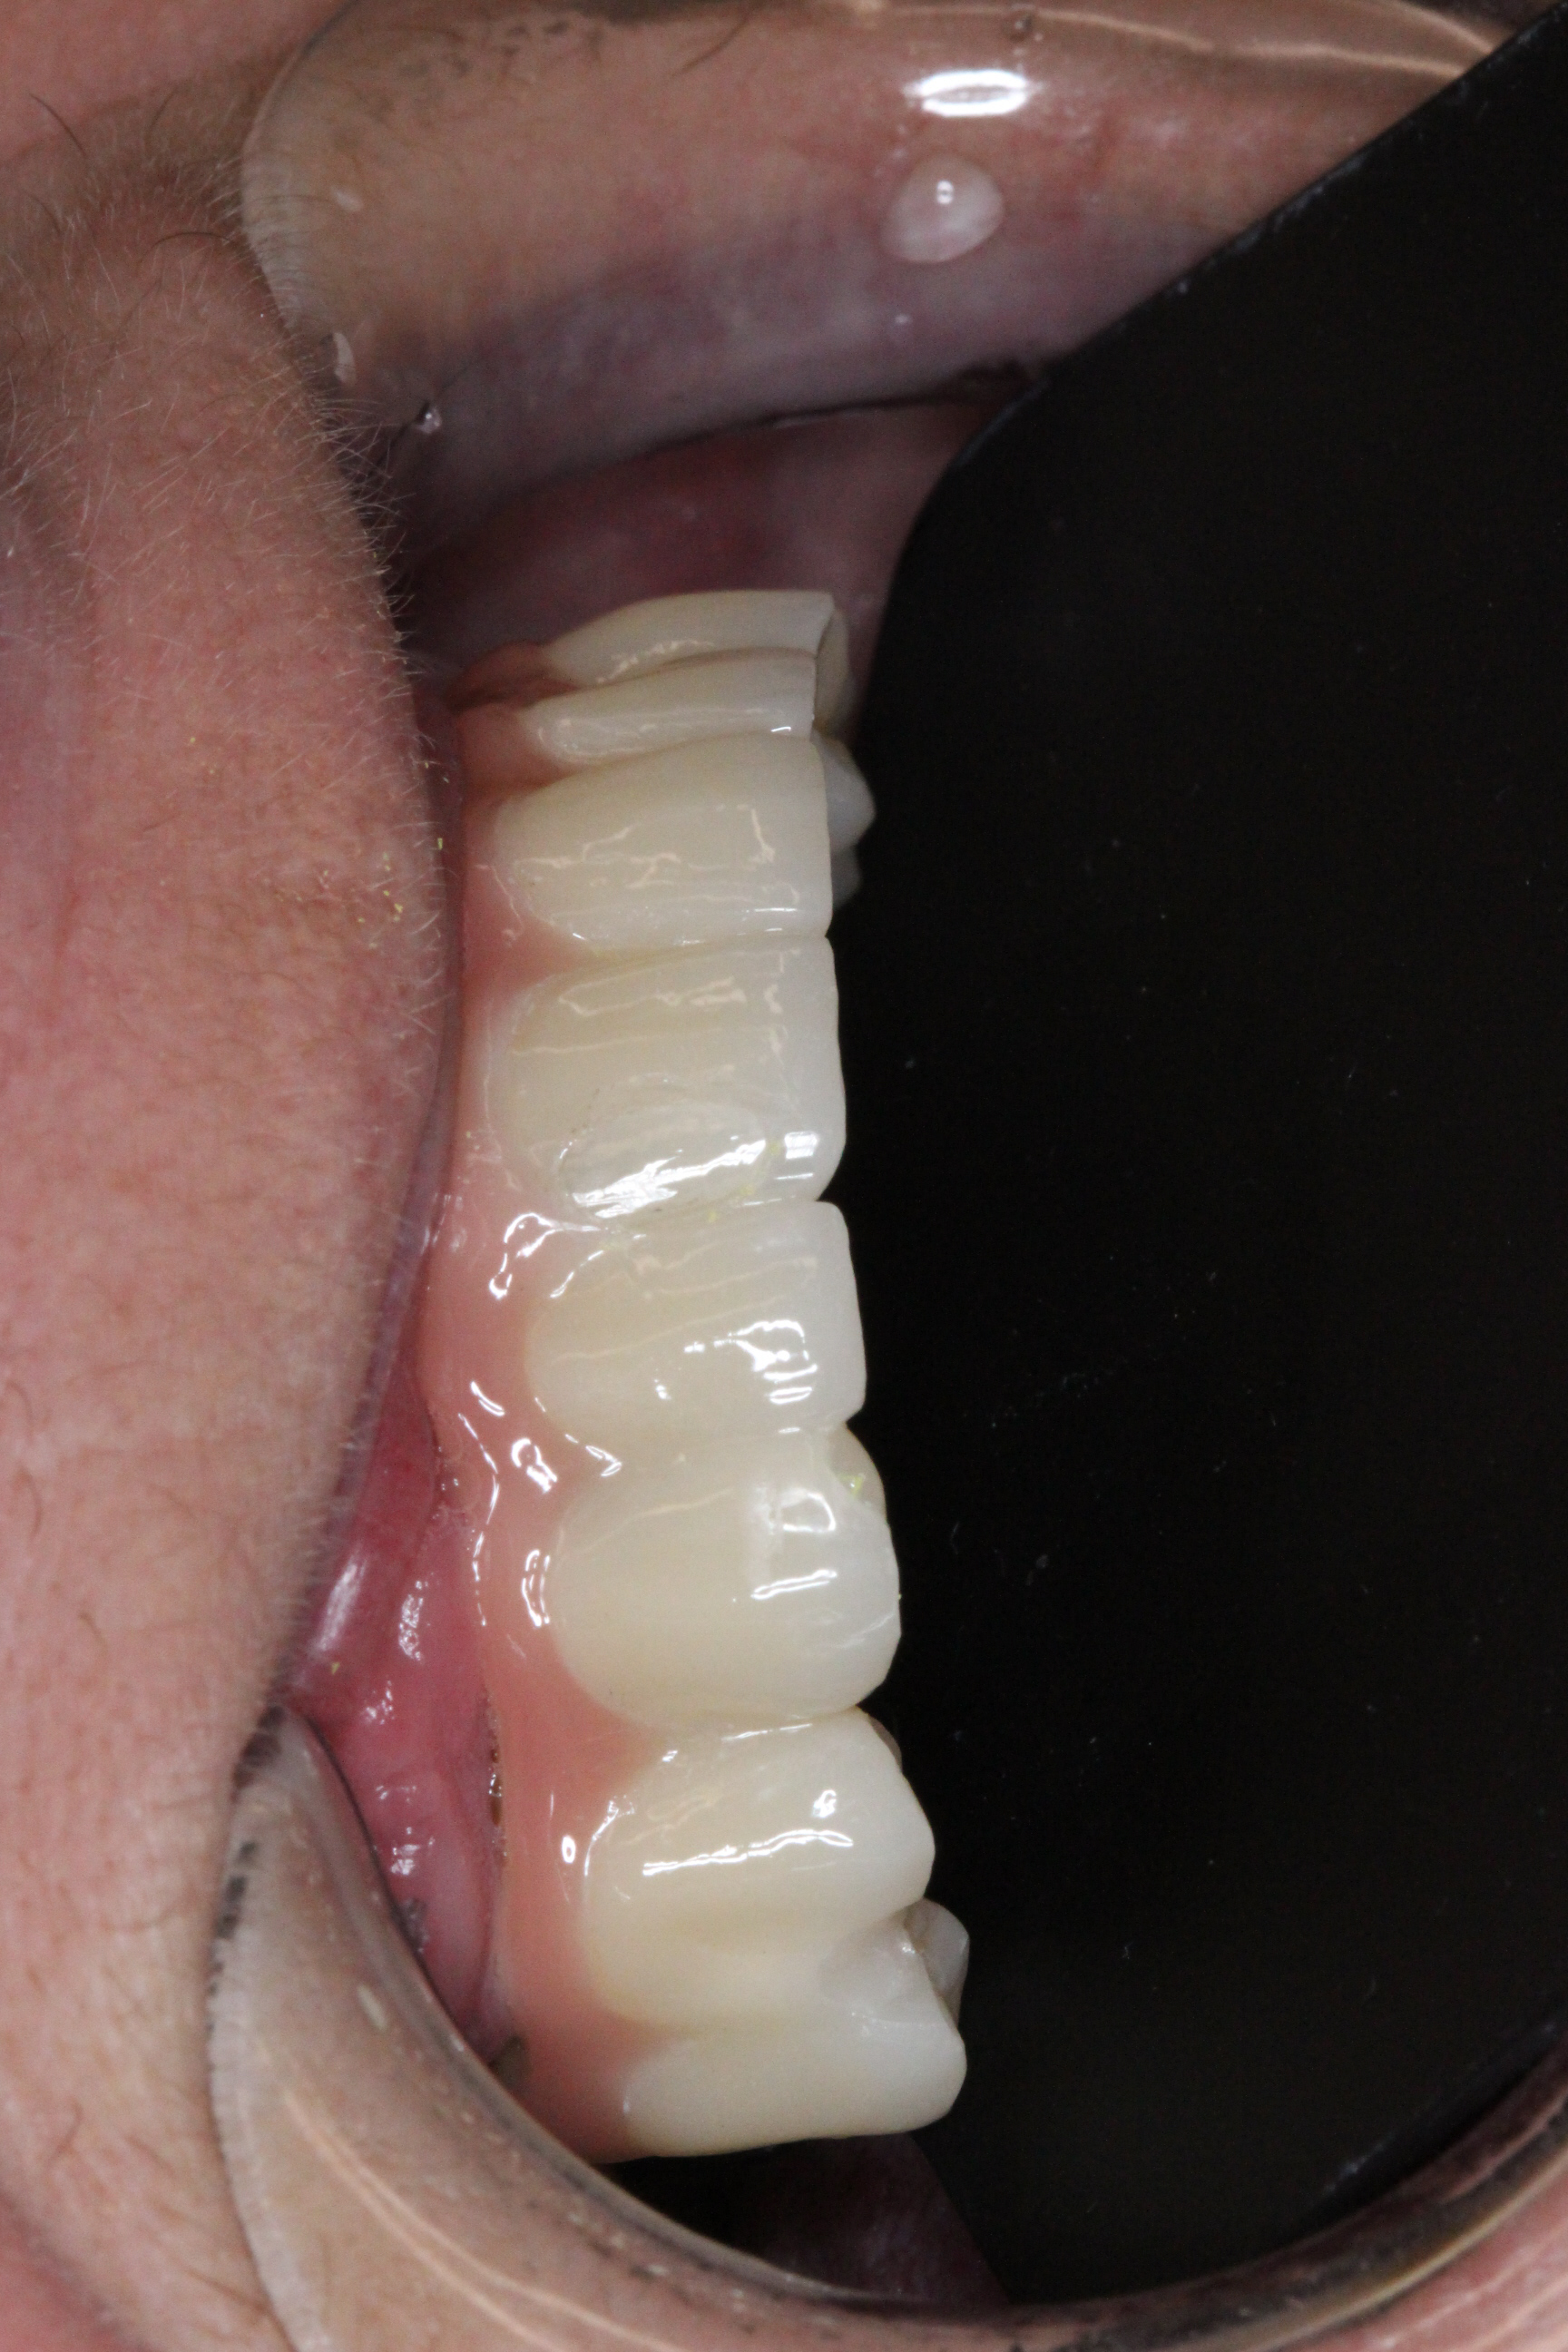

Two weeks later, the patient received her FP2 suprastructure, which was mounted using prosthetic screws. The screw access openings were sealed with composite, and custom-made zirconia posts were placed where visible for optimal esthetics.